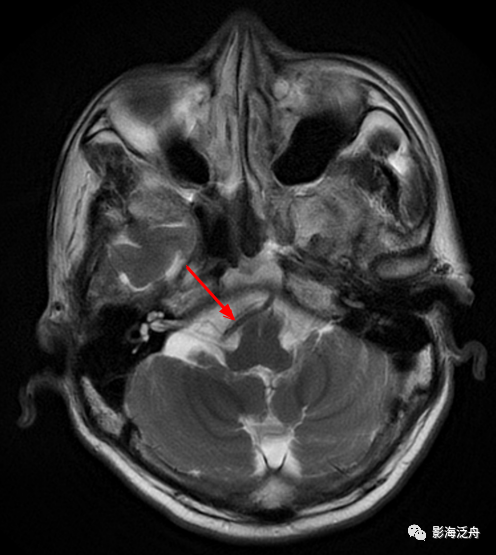

海绵窦、CPA区病变

左侧颈内动脉海绵窦段动脉瘤

伴血栓形成(红箭),绿箭为海绵窦段起始端,黄箭头所指为颈内动脉分段的重要解剖标志——前床突(颈内动脉分段可参考之前的文章 颈内动脉CTA分段(超实用))。

海绵窦周围除了动脉瘤外,占位性病变也比较常见,如脑膜瘤、神经鞘瘤、脑外海绵状血管瘤

等。